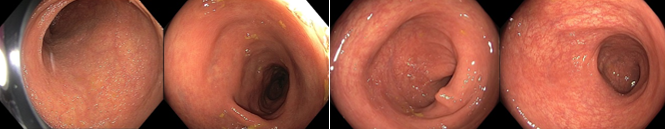

018/2 Slizniční zhojení. Monoterapie vedolizumabem

2022/9 klinická, laboratorní i endoskopická remise

Slizniční zhojení